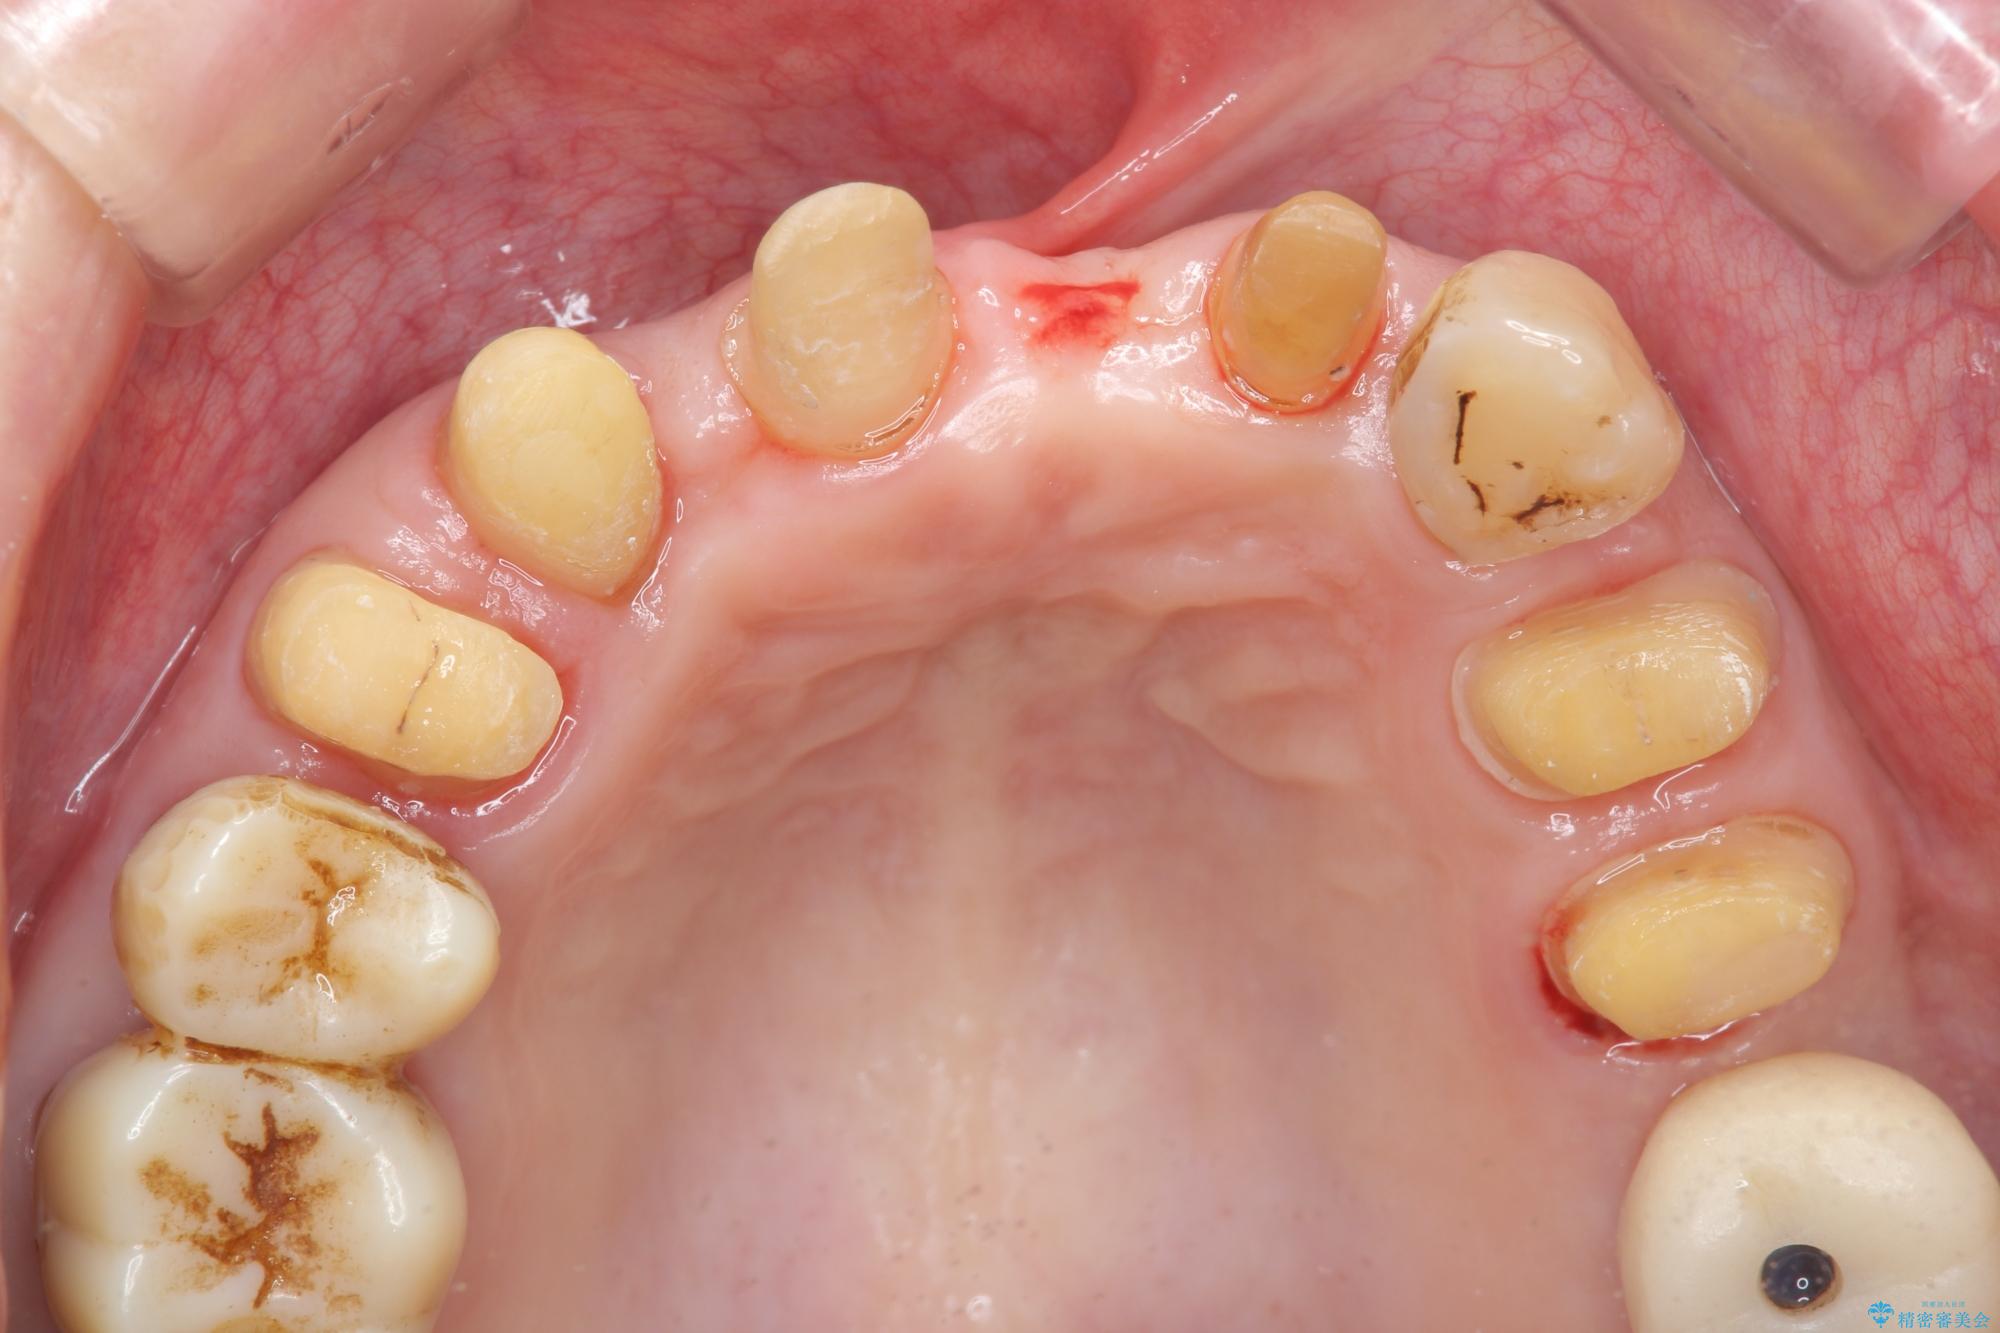

治療中

歯の総合的なマネージメントを行う包括的歯科治療の実践[ 歯周病・矯正・セラミック補綴 ] 治療中画像 歯の総合的なマネージメントを行う包括的歯科治療の実践[ 歯周病・矯正・セラミック補綴 ] 治療中画像 歯の総合的なマネージメントを行う包括的歯科治療の実践[ 歯周病・矯正・セラミック補綴 ] 治療中画像 歯の総合的なマネージメントを行う包括的歯科治療の実践[ 歯周病・矯正・セラミック補綴 ] 治療中画像 歯の総合的なマネージメントを行う包括的歯科治療の実践[ 歯周病・矯正・セラミック補綴 ] 治療中画像 歯の総合的なマネージメントを行う包括的歯科治療の実践[ 歯周病・矯正・セラミック補綴 ] 治療中画像 歯の総合的なマネージメントを行う包括的歯科治療の実践[ 歯周病・矯正・セラミック補綴 ] 治療中画像 歯の総合的なマネージメントを行う包括的歯科治療の実践[ 歯周病・矯正・セラミック補綴 ] 治療中画像 歯の総合的なマネージメントを行う包括的歯科治療の実践[ 歯周病・矯正・セラミック補綴 ] 治療中画像 歯の総合的なマネージメントを行う包括的歯科治療の実践[ 歯周病・矯正・セラミック補綴 ] 治療中画像 歯の総合的なマネージメントを行う包括的歯科治療の実践[ 歯周病・矯正・セラミック補綴 ] 治療中画像